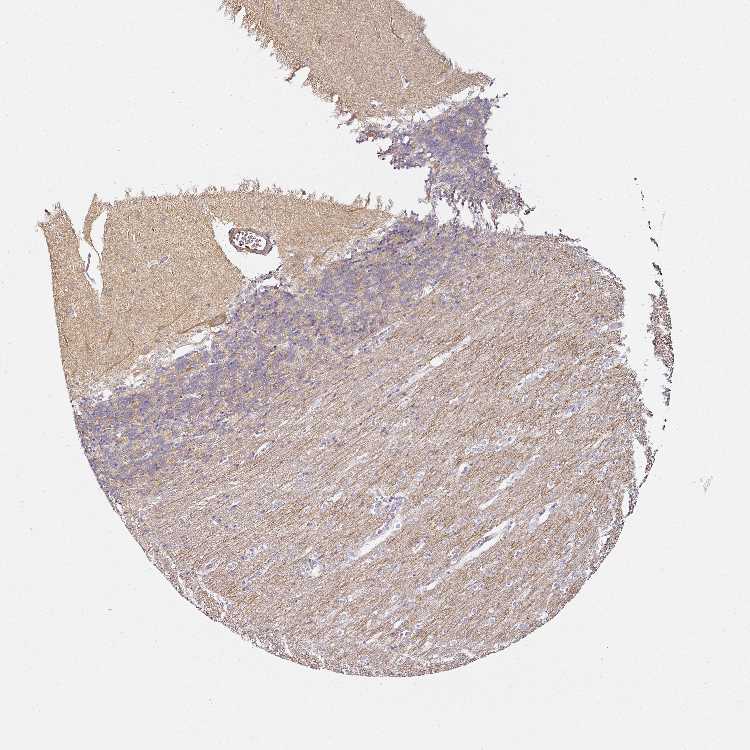

CEREBELLUM - Antibody stainingi

Antibody staining in the annotated cell types in the current human tissue is reported as not detected, low, medium, or high, based on conventional immunohistochemistry profiling in selected tissues. This score is based on the combination of the staining intensity and fraction of stained cells.

Each image is clickable and will lead to virtual microscopy that enables deeper exploration of all samples and also displays staining intensity scores, fraction scores and subcellular localization as well as patient and tissue information for each sample.

Antibody HPA050530Antibody HPA054147

Purkinje cells - cytoplasm/membrane High-

Purkinje cells - dendrites High-

Processes in granular layer High-

Processes in white matter High-

Synaptic glomeruli - core Medium-